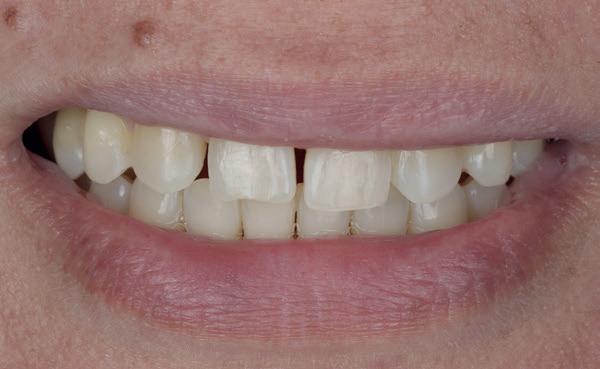

Op 16-jarige leeftijd werd de patiënt door haar behandelend orthodontist naar de auteur verwezen voor een restauratieve oplossing voor de afwezige 11 en 21. In de tussenliggende periode had patiënt een retainer gedragen met twee kunststof tanden (afbeelding 1). Zowel de patiënt als haar moeder hadden een sterke voorkeur voor een implantaat gedragen vaste oplossing. Gezien haar jonge leeftijd was dit echter nog geen optie, omdat er nog verticale groei te verwachten viel. Implanteren op jonge leeftijd – dat wil zeggen vóór het 21e levensjaar – kan resulteren in een infrapositie van het implantaat, omdat de rest van het gebit nog verticaal kan doorgroeien.

Middels shared decision making werd het volgende plan overeengekomen: eerst zou er een etsbrug met vleugels op de 12 en 22 worden vervaardigd, om op 21-jarige leeftijd verder te gaan met implantologie.

Bij klinisch en röntgenologisch onderzoek viel echter op dat radix van de 12 en 22 een convergerende (de radices staan dan naar mesiaal en naar elkaar toe) in plaats van divergerende (radices staan dan van elkaar af) stand had. Door deze convergerende stand van de radices was er in mesio-distale zin geen ruimte voor twee implantaten ter plaatse van de 11 en 21. Er werd daarom besloten, in tegenzin

1. Retainer met twee frontelementen

2. OPT radices 12 en 22 convergeren

3. Vaste apparatuur voor torque 12 en 22

4. OPT radices 12 en 22 divergeren na orthodontische behandeling

van de patiënt, om eerst weer vaste apparatuur terug te plaatsen om de radices in een divergerende stand te plaatsen. Gelukkig verliep deze behandeling voorspoedig. (afbeelding 2 -4). Het volgende behandelplan werd gemaakt:

• Intra-orale scan voor studiemodellen, proefopstelling en beoordelen ruimte palatinaal

Vervaardigen essix retainer met dummies waarbij er een emergence profile van de 11 en 21 werd gevormd door eivormige dummies 4 mm in de gingiva te plaatsen

• Aanvulling zachte weefsels met de VISTA techniek en een vrij gingivatransplantaat uit het palatum links en direct dragen van de essix retainer

Na 4 weken intra-orale scan voor de etsbrug en kleurbepaling bij de technicus

• Plaatsen van de etsbrug met een composietcement

Voordat er gescand kon worden voor een etsbrug, werd een studiemodel vervaardigd om met de technicus te overleggen of er voldoende ruimte was voor 2 centrale incisieven in de mesio-distale zin en of er voldoende ruimte was in occlusie voor de vleugels van de etsbrug. Er hoeft enkel nog aan de 12 en 22 pala-

tinaal geslepen te worden als er geen 1,5 mm ruimte voor de vleugels behaald kan worden. De ruimte was op de dunste plekken 1 mm, dus een kleine preparatie in de 12 en 22 palatinaal was nodig. Omdat de kaak volledig afgevlakt was en dun was geworden, kunnen de dummies van de etsbrug enkel op de kaak “gelegd worden”, maar daarbij zijn er geen papillen en staat de cervicale rand van de dummies net voor de kaak. Een esthetisch resultaat kan daarmee niet behaald worden. Daarom is een aanvulling van de zachte weefsels in de breedte nodig, als het creëren van een emergence profile, waarbij het oogst alsof de gebitselementen uit het weefsel vertrekken.